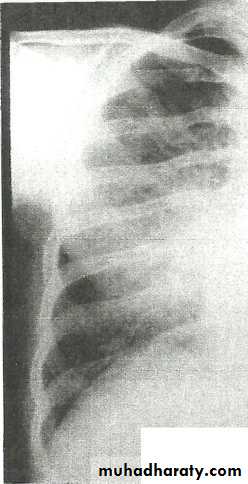

Encapsulated fluid

(A) PA and (B) lateral chest radiographs. Pleural fluid is encapsulated in the major fissure and against the anterior chest wall. These encysted fluid collections can mimic a lung tumour.